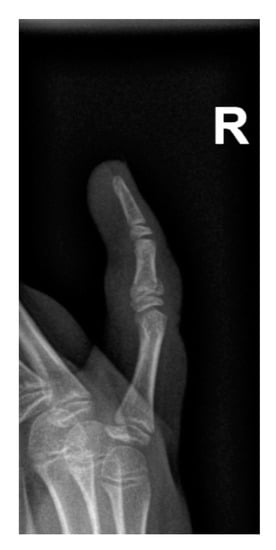

Only 21 Salter–Harris fractures were observed, accounting for 1.46% of all injuries and 3.36% of all fractures, with type II being dominant (Table 4). Due to the low number of cases, performing a reliable statistical analysis was impossible. An example of a Salter–Harris fracture is presented in Figure 8.

Figure 8. Example of a Salter–Harris fracture of the intermediate phalanx of the fifth finger on the right hand.